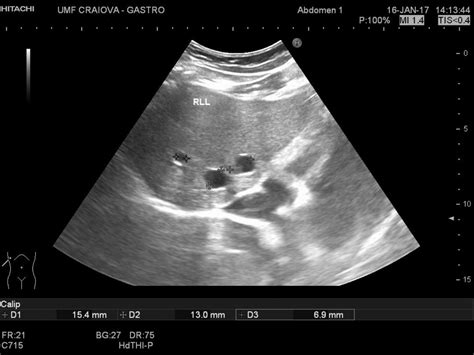

A liver ultrasound cyst is a fluid-filled sac that develops within the liver. These cysts can vary in size and number and are often discovered incidentally during routine imaging tests. Liver cysts can be classified into two main types: simple cysts and complex cysts. Simple cysts are benign and typically do not cause symptoms, while complex cysts may require further investigation due to the potential for malignancy.

The diagnosis of liver ultrasound cysts typically involves a combination of imaging tests and clinical evaluation. The primary diagnostic tool is the liver ultrasound, which provides detailed images of the liver and surrounding tissues. Additional tests may include:

• hepatic cyst ultrasound images

• simple cyst liver ultrasound